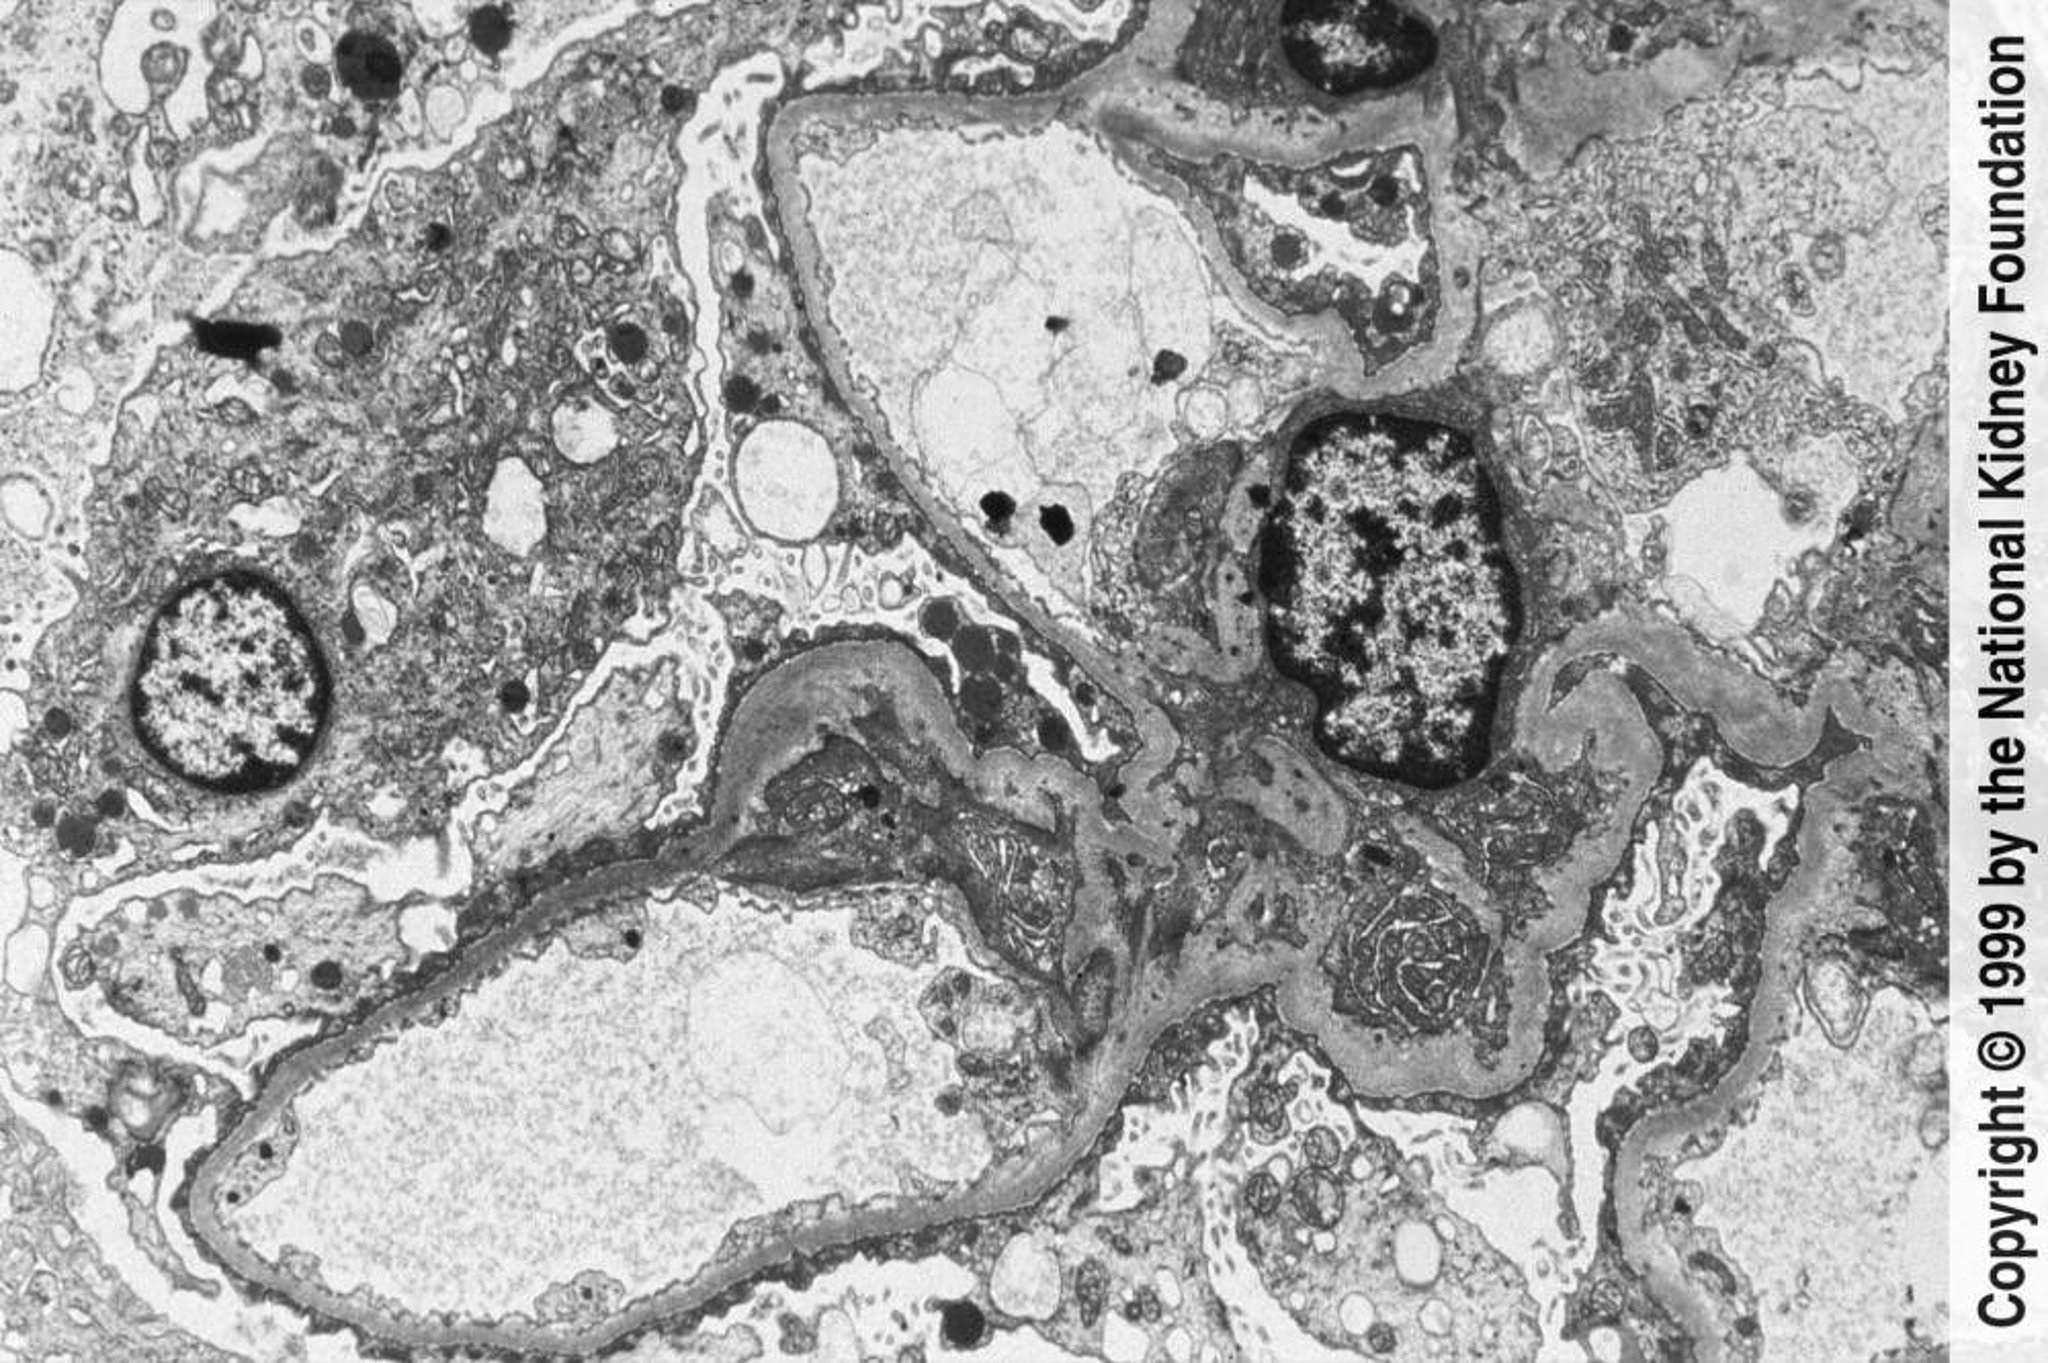

Focal Segmental Glomerulosclerosis (Blunting and Effacement of Foot Processes)

Extensive blunting and effacement of foot processes can be seen on transmission electron microscopy (×3000).

Image provided by Agnes Fogo, MD, and the American Journal of Kidney Diseases' Atlas of Renal Pathology (see www.ajkd.org).